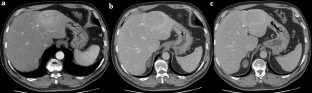

Fig. 3